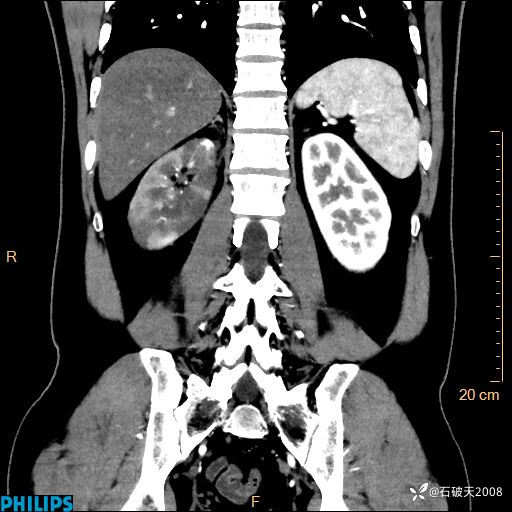

这个病例诠释了“腹部不增强,等于耍流氓”

男 44岁 主 诉:右侧腰背部疼痛4天。

现病史:4天前无明显诱因出现右侧腰背部疼痛,呈阵发性发作,疼痛性质描述不详,无尿频、尿急、尿痛,无恶心呕吐、腹泻、黑便,无胸闷、胸痛、呼吸困难,无发热、寒颤等,休息后缓解不明显,昨日到我院门诊就诊,行泌尿系彩超示:1.双肾肾砂;2.前列腺体积稍大。予“肾石通丸”、“左氧氟沙星片”等药物口服治疗后无缓解,昨日夜间再次到我院就诊,急诊科予“复方双氯芬酸钠注射液”肌注处理后好转,今晨仍感右侧腰背部疼痛,再次来诊并由门诊以“腰痛”为初步诊断收入我科。发病来患者神志清,精神稍差,饮食睡眠欠佳,小便正常,大便不畅,体重近期无下降。

冠状位